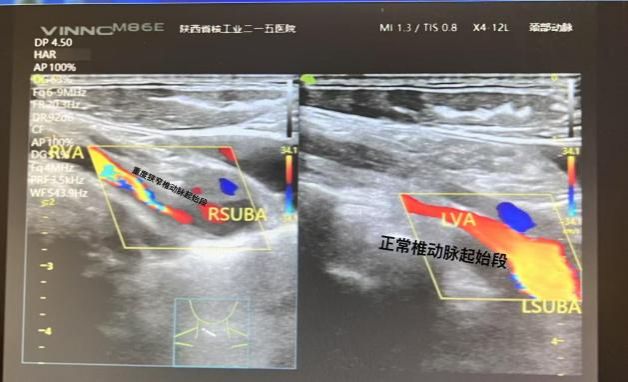

1.颈部血管超声——看透颈部的“公路”

这项检查就像一位道路维修工,用探头在您的颈部皮肤上滑过,就能清晰地看到:

血管内壁是否增厚了?

有没有长斑块?斑块有多大、稳不稳定?

血管有没有变窄,变窄了多少?

它能帮助医生判断您的颈部大血管健康状况,及时发现中重度狭窄,为是否需要进一步手术(如颈动脉内膜剥脱术或支架植入)提供重要依据。